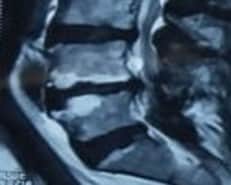

After obtaining informed consent, the patient was taken to the operating theatre. Antibiotics were administered by peripheral venous access to prevent infection before intradiscal PRP injection. PRP was made by the department of transfusion medicine, ShSMCH, and the platelet count was more than 1000000/ml. The patient was placed in a prone position on the X-ray operating table, and the L4-5 level was identified by counting vertebrae from X-ray images. With all aseptic precautions, the skin was infiltrated with 1% lignocaine. Then, a spinal needle (22-gauge, 150mm) was inserted into the nucleus pulposus (NP) of the L4/5 disc in the anteroposterior (AP) and lateral views under intermittent fluoroscopy. Approximately 2 mL of PRP was slowly injected through a syringe into the disc. After the procedure, the patient was observed in the post-operative ward for about an hour and found uneventful. The patient was advised to do activities of daily living and physical activity, such as exercise, at 7 days and 1 month postinjection, respectively. She was also advised not to take steroids and non-steroidal anti-inflammatory drugs (NSAIDs) for about 1 month, except in the case of particularly severe pain (VAS scores of 8 points or more). Follow-up surveys, including VAS, RMDQ, and any side effects, were carried out by phone at 1 week, 1 month, 3 months, 6 months, and 12 months following intradiscal PRP injections. Quality of life by SF-12 was measured after 1 month, 6 months, and 12 months. Subsequently, a follow-up MRI of the lumbar spine was done after 6 months of injection. Figure 1 shows the Modic change before and after PRP injection. A decrease in high signal intensity on T2WI was seen after PRP injection in the intervertebral disc at the L4/5 disc.

MRI shows modic change before (a,b) and after (c,d) PRP injection

Figure 1: MRI shows modic change before (a,b) and after (c,d) PRP injection

The process of Modic change in our patient was somehow reversed by PRP injection. This autologous platelet-rich plasma mimics the physiological repair process by releasing autologous growth factors (GFs) and creating a transient biological matrix. It can be considered that PRP treatment could stimulate the endogenous repair machinery and induce the healing of damaged spinal components to ultimately restore disc and vertebral bone homeostasis and an improvement in the functional anatomy of the end plate.[20] It is difficult to determine whether Modic type 1 is the cause of LBP. Discography may be necessary to diagnose Modic change accurately as the cause of LBP. However, discography, an invasive test, was not performed in this study because a significant association was established between MC and LBP.[25]

Only a few reports demonstrate MRI improvements in disc degeneration and Modic change after PRP treatment. As MRI provides more detailed information, the case presented here shows appreciable MRI improvements in terms of decreasing high-signal intensity on T2WI after 6 months of PRP therapy.[20,25] Other modalities like intradiscal steroid injections, anti-tumor necrosis factor (TNF)-α antibodies, and antibiotic administration, have been reported to have short-term efficacy in Modic change, but long-term results are unknown. Albert et al. treated patients with Modic type I with antibiotics for 100 days and reported that the VAS of patients with LBP improved from 67 to 37 mm after 1 year.[27]